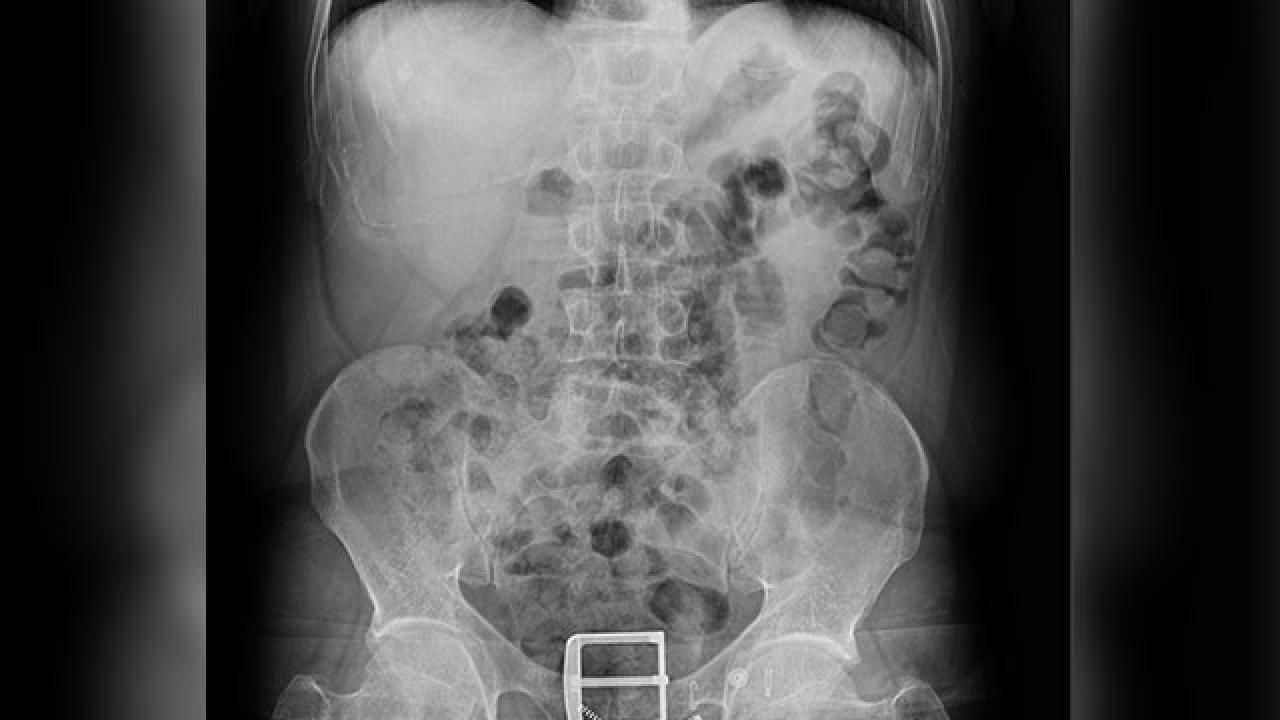

4 şüphelinin çekilen röntgenlerinde midelerinde 121 parça halinde 840 gram eroin tespit edildi. Uyuşturucular, yapılan tedavinin ardından çıkarıldı.